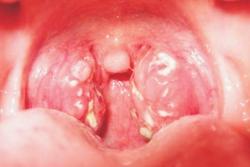

Thiết lập phương án phòng, chống dịch bệnh sởi

Sau thời gian tiến hành điều tra, giám sát dịch tễ, đánh giá nguy cơ về tình hình bệnh sởi trên địa bàn tỉnh, nhiều giải pháp đã được ngành y tế đưa ra để phòng chống dịch bệnh này lây lan rộng.